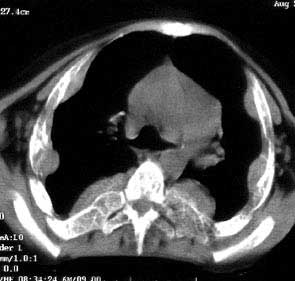

以下是引用jiajie在2004-12-10 22:14:53的发言:[br]多发性肋骨骨质疏松,[br][br]麦粒状及筛孔状骨质破坏,[br][br]髓腔膨胀皮质变薄,[br][br]骨旁多发软组织肿块,[br][br]考虑恶性病变,支持肋骨多发性骨髓瘤。

以下是引用pujunzhi在2008-7-3 21:21:00的发言:[br]支持地中海贫血伴髓外造血可能性大,需与多发性骨髓瘤、淋巴瘤等鉴别。